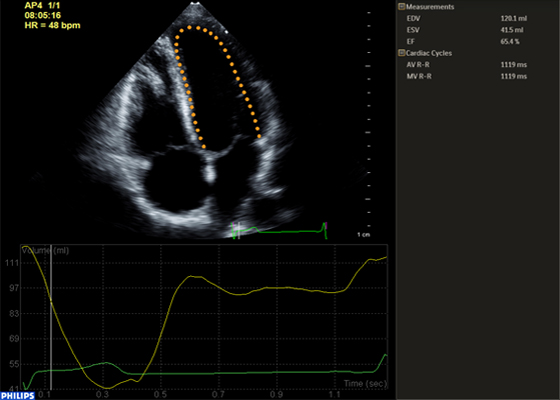

Функция интеллектуального определения анатомических структур изучает данные УЗИ пациента и применяет адаптивную интеллектуальную логику системы с использованием трехмерных анатомических моделей для создания более простых и воспроизводимых результатов. Инструменты интеллектуального определения анатомических структур, например HeartModel, используют усовершенствованное моделирование органов, формирование срезов изображений и надежный количественный анализ, помогая упростить проведение УЗИ, обеспечивая более высокую воспроизводимость, предоставляя при этом клиническую информацию нового уровня для решения экономических и клинических задач, возникающих в условиях современного медицинского учреждения.

Инструменты интеллектуального определения анатомических структур превращают изображения в ответы